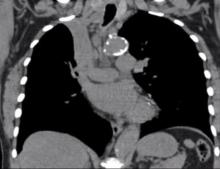

The author demonstrates the technique for a VATS sleeve lobectomy in an 82-year-old woman. A three-port technique is used, with a 5 mm, 10 mm, and a utility port. To optimize the view, the camera is moved from the anterior to the posterior port during the procedure and back, depending on the region of dissection. Management of mediastinal pleural involvement by a post obstructive pneumonic process, failure of the thymic flap, and subsequent harvest and use of an intercostal flap are all demonstrated.